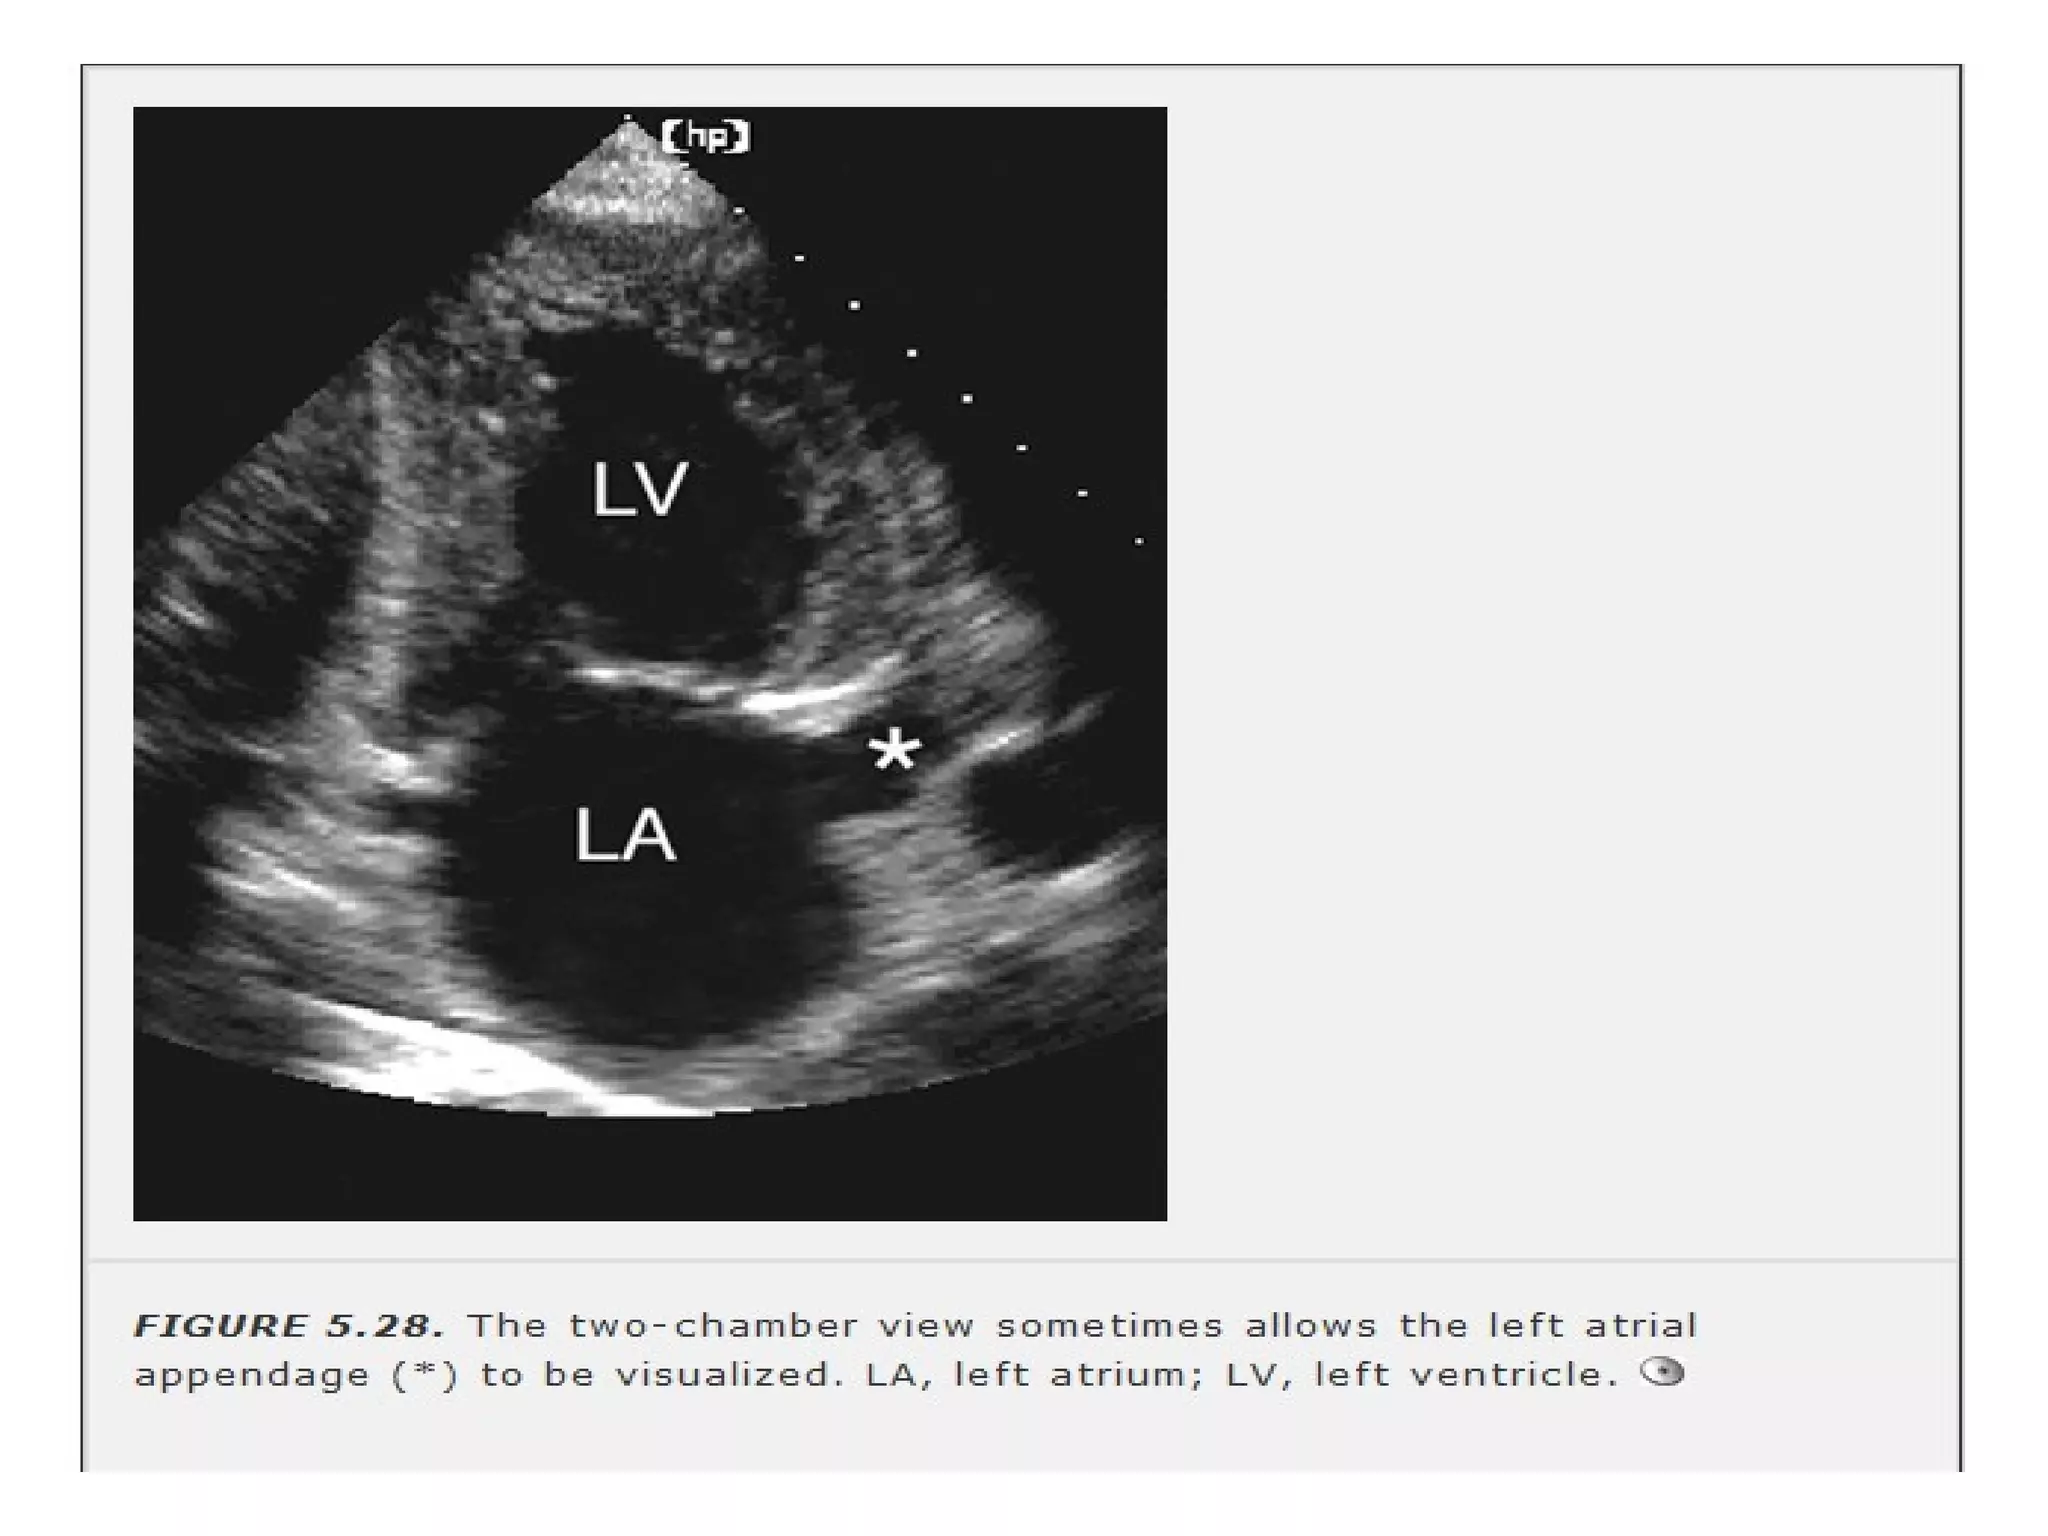

• Apical 2 chamber- rotating the transducer

CCW approx 60 deg.

Similar orientation to RAO

angiographic view LA

APPENDAGE IS VIEWED.